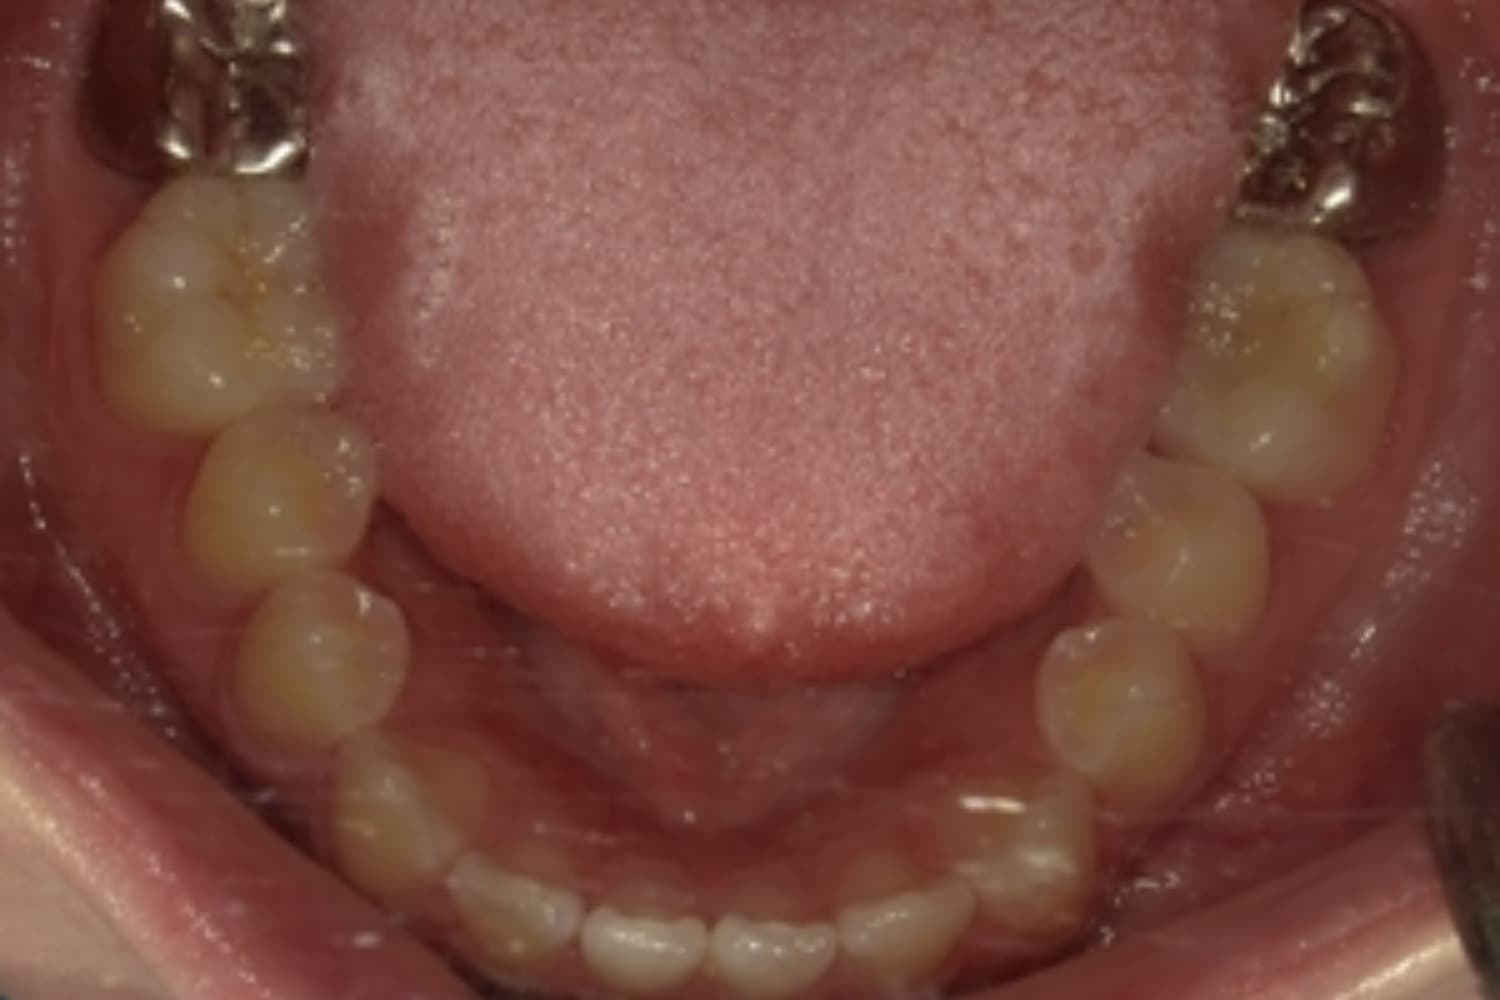

下顎大臼歯3本欠損症例

Before

After

左下第一大臼歯は保存が困難な状態であったため抜歯をおこないました。あわせて、ご来院時から欠損していた右下第一・第二大臼歯も含め、欠損部の補綴方法についてご説明し、インプラント治療を選択されました。

年齢

60歳

性別

男性

主訴

左下の第一大臼歯は別の医院で治療中でしたが、治療が思うように進まず、加えて他の箇所にも痛みが続いたことから、当院にご相談いただきました。

治療期間

10ヵ月

費用

140万円

副作用・リスク

インプラント治療は外科的な処置を伴い、多少の腫れや痛みが出ることがあります。 多くの場合は鎮痛薬で和らげることができます。